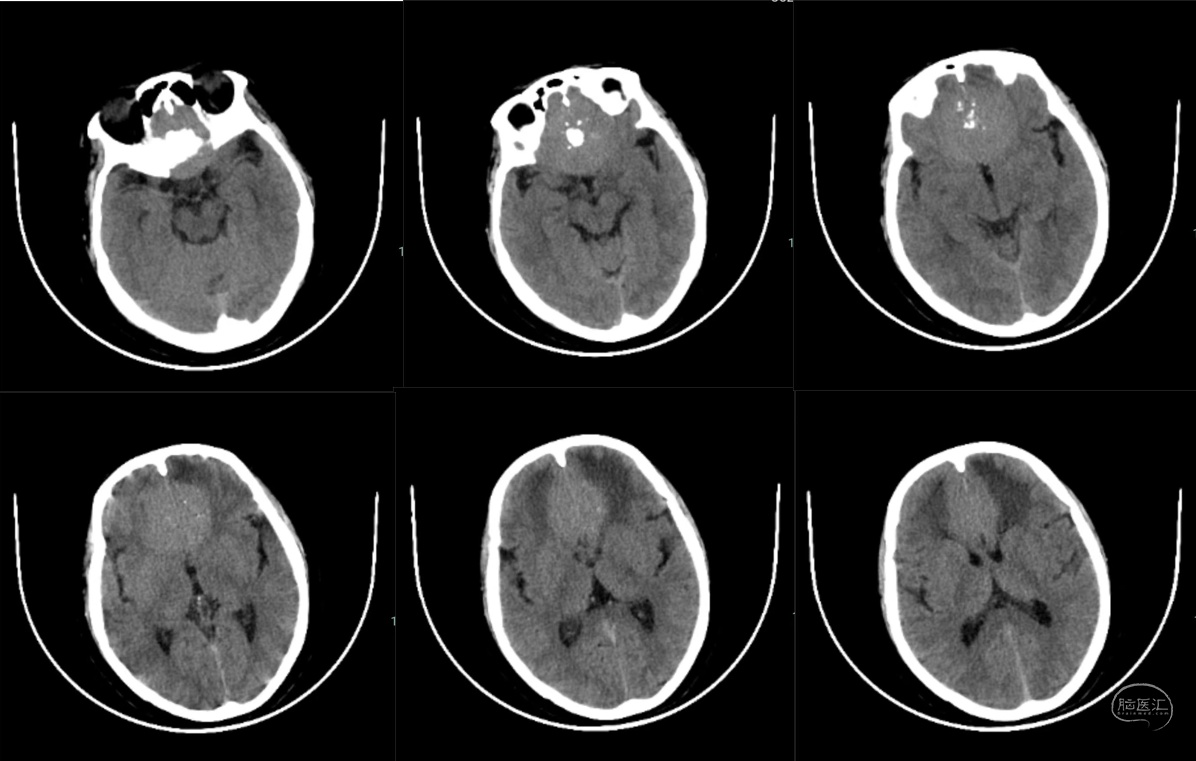

颅脑CT:前颅底占位性病变,颅底骨质增生,瘤内钙化,周围脑组织水肿。

注:术后第一天CT显示额叶脑挫伤及水肿不重